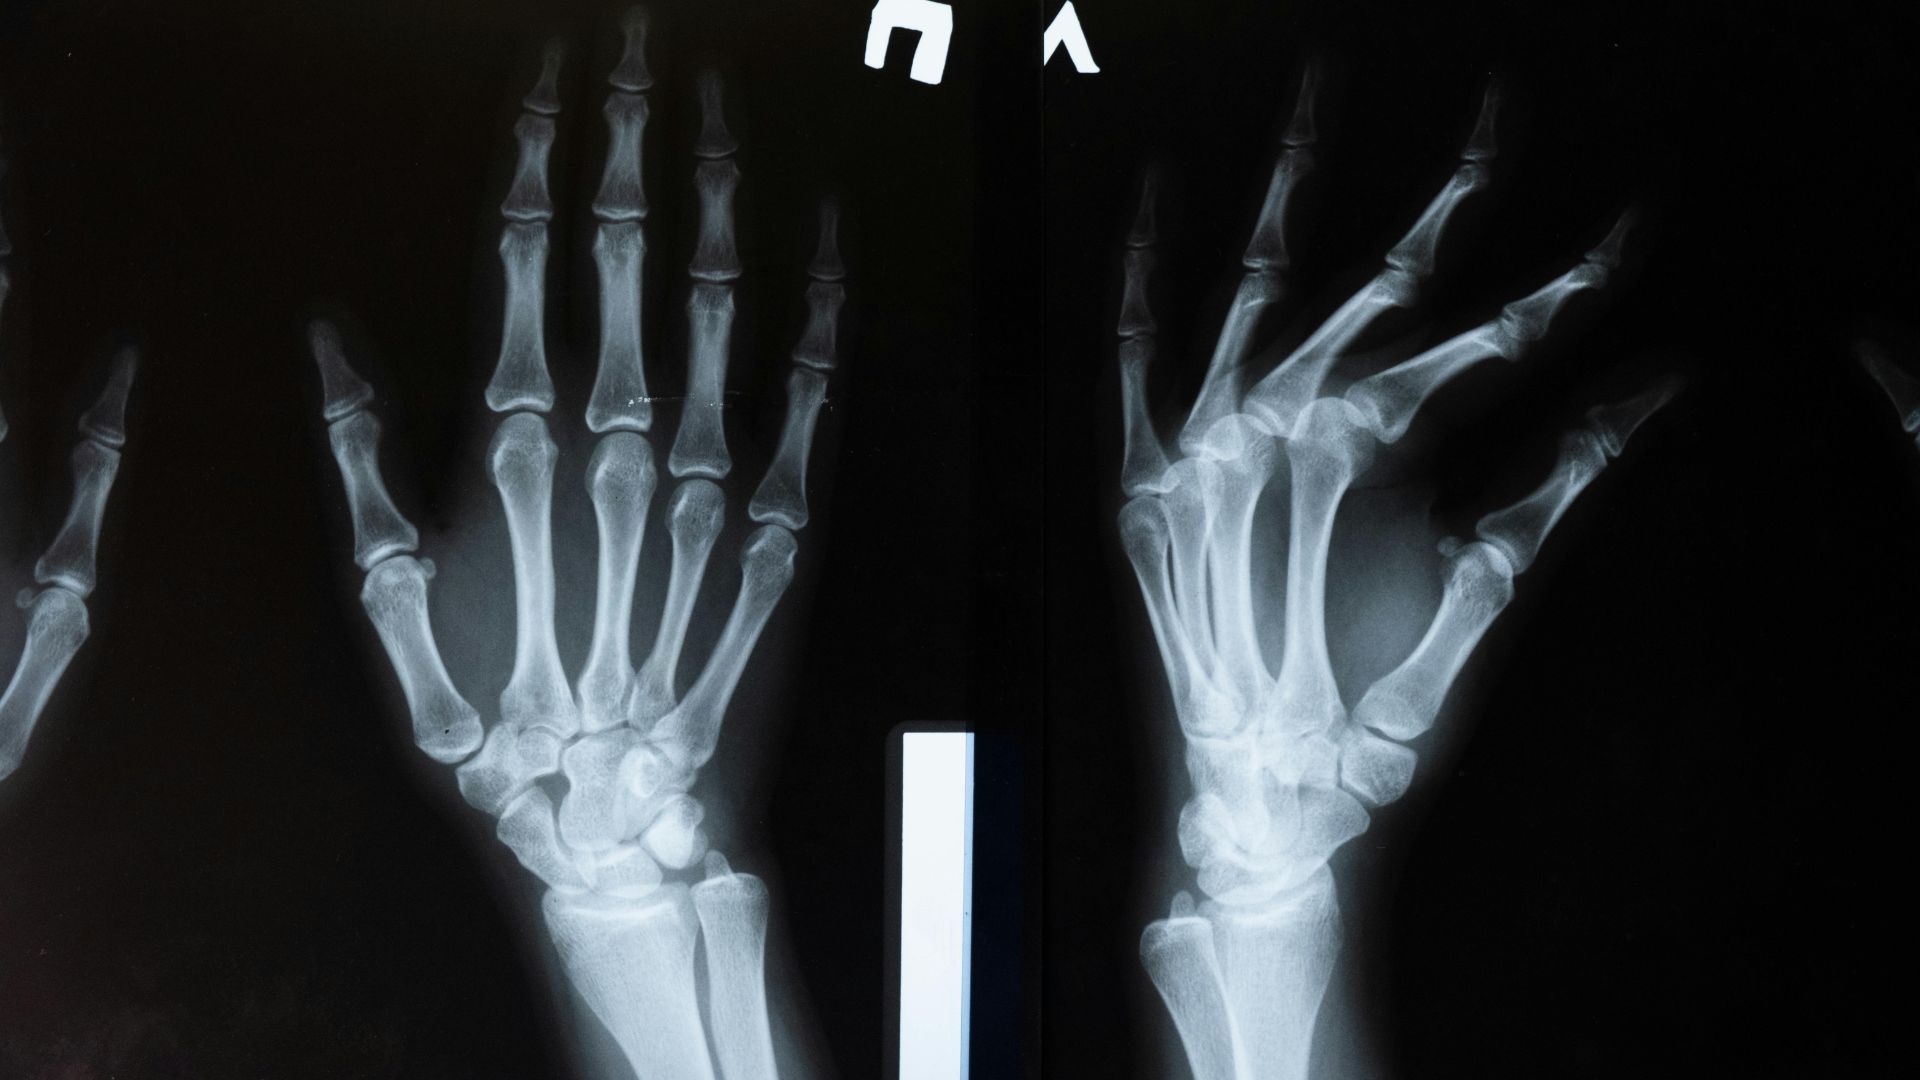

Chẩn đoán hình ảnh:

- X-quang: X-quang thường là lựa chọn đầu tiên để kiểm tra cấu trúc xương, gãy xương, các dấu hiệu viêm khớp, thoái hóa, u xương hoặc dị vật. Tuy nhiên, X-quang hạn chế trong việc quan sát mô mềm (gân, dây chằng, sụn), do đó có thể cần kết hợp các kỹ thuật khác.